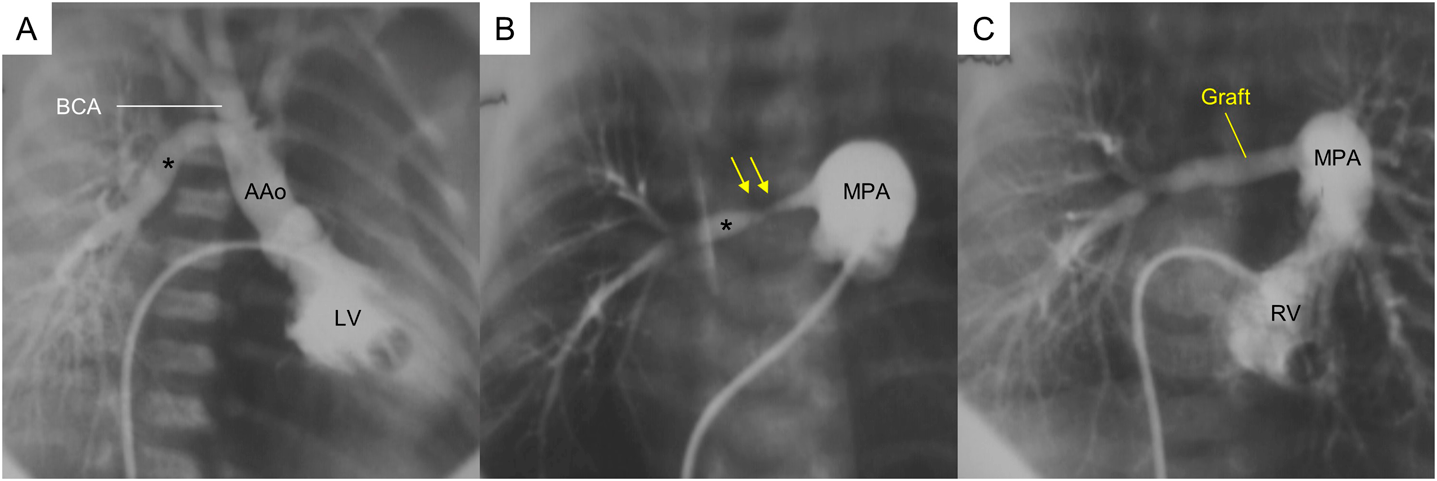

A boy weighing 3.0 kg, with AORPA of the distal form, aortic arch hypoplasia, atrial septal defect, and patent ductus arteriosus (PDA), underwent primary surgical repair at 7 days old. The results of a PDA occlusion test revealed a significantly reduced descending aortic pressure, which was consistent with CoA. After the CoA repair with an extended aortic arch anastomosis, the right pulmonary artery (RPA) arising immediately proximal to the bracheocephalic artery (Fig. 1A) was transected at its origin and reconstructed with direct anastomosis to the main pulmonary arterial trunk (MPA) behind the ascending aorta (AAo). Postoperative MPA angiography illustrated a diffuse stenosis of the proximal RPA (Fig. 1B). Subsequently, the patient underwent the second operation for excision of the stenotic lesion and graft interposition using a 5-mm expanded polytetrafluoroethylene graft (Gore-Tex; W.L. Gore and Associates, Flagstaff, AZ, USA) behind the AAo at 1 month following the initial operation. The histological specimen of the excised vessel proved to have a remnant of a PDA tissue. Postoperative cardiac catheterization showed a large RPA that had been reconstructed without compression from the AAo, and the ratio of pulmonary to systemic arterial pressures decreased from 1.0 to 0.31 (Fig. 1C). Nine years later, the artificial graft was upsized to a 14-mm expanded polytetrafluoroethylene graft. This patient is currently 25 years old and remains healthy.

A: Preoperative left ventriculogram.B: Pulmonary arterial angiogram after the initial repair. C: Rght ventriculogram after revision of the right pulmonary artery. AAo, ascending aorta; BCA, bracheocephalic artery; LV, left ventricle; MPA, main pulmonary arterial trunk; RV, right ventricle. Black asterisk: right pulmonary artery; yellow arrows: stenosis.